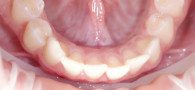

В клинику «Виртуоз» обратилась пациентка с жалобами на неудовлетворённость улыбкой из-за неровного расположения зубов в верхнем ряду.

После консультации и диагностики врач-ортодонт Антонина Ивановна предложила ортодонтическое лечение брекетами.

В общей сложности лечение длилось 15 месяцев. В результате пациентка обрела ровные красивые зубы и стала больше улыбаться.

Ортодонтическое лечение

Ортодонтическое лечение включало в себя установку брекетов с их регулярной ежемесячной корректировкой в Центре стоматологии «Виртуоз». После окончания лечения пациентке было назначено ношение ретейнеров для надёжного результата. В итоге всего за год и три месяца она обрела улыбку, о которой мечтала с детства.